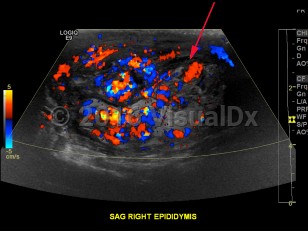

Epididymo-orchitis

Symptoms of epididymo-orchitis usually develop over 1-2 days, although some patients will complain of a more gradual onset of symptoms. The primary complaint is swelling of the scrotum associated with pain. Urethral discharge is common. Fever may or may not be present. On palpation, swelling in the posterior scrotum localized over the involved epididymis can be appreciated. There may be a hydrocele. There may be erythema overlying the area of swelling. Pain should improve within 72 hours after treatment, although inflammation may persist for a few weeks.